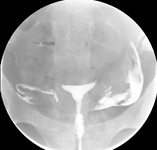

Normal saline infusion ultrasound

From the collection of Dr Jared C. Robins